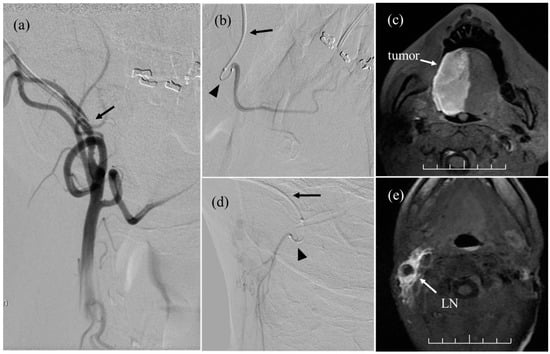

- Ii, N.; Fuwa, N.; Toyomasu, Y.; Takada, A.; Nomura, M.; Kawamura, T.; Sakuma, H.; Nomoto, Y. A novel external carotid arterial sheath system for intra-arterial infusion chemotherapy of head and neck cancer. Cardiovasc. Interv. Radiol. 2017, 40, 1099–1104. [Google Scholar] [CrossRef]

- Nomura, M.; Fuwa, N.; Toyomasu, Y.; Takada, A.; Ii, N.; Nomura, J.; Yamada, H. A comparison of two types of microcatheters used for a novel external carotid arterial sheath system for intra-arterial chemotherapy of head and neck cancer. Jpn. J. Radiol. 2018, 36, 622–628. [Google Scholar] [CrossRef]